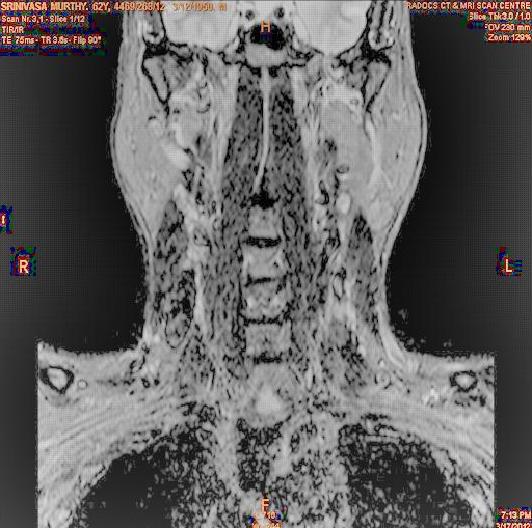

The developed algorithm presented in the previous section was coded using Matlab Version 8.0. The experiment was conducted by considering poor quality spinal cord images of having various lesions. The first column of Fig. 4 shows the axial view of neck spinal cord images of size pixels, respectively. The second column of Fig. 4 presents the same images enhanced using histogram equalization. As is evident from the results presented, the histogram equalization method performs global image enhancement operation which improves the contrast of an image but at the cost loss in image details. The third column of Fig. 4 shows the MSR based spinal cord image enhancement. It can be seen that from the result presented, MSR scheme improves the details that are not clearly visible in histogram equalization technique. In general, image enhancement achieved by MSR method is better compared to histogram equalization. However, the MSR method voilates gray world assumption. Therefore, the image enhanced by this scheme appears to be grayish. Although, numerous work have been reported for solving the problem due to gray world voilation, no work seems to developed for complete elimination.

The fourth column of Fig. 4 shows the image enhanced using Chao et al. []. It can be seen from the results presented that the reconstructed images of Chao’s method have black spots. The appearance of these dark patches degrades the visual quality of the enhanced image. The image enhanced using proposed multirate multiscale retinex image enhancement method presented in the fifth column of Fig. 4, overcomes the drawback of the Chao’s method. As we can see from the simulation results, image enhancement achieved by the proposed method has improved details with significant contrast enhancement. The enhanced images from the proposed method provides information to physicians, radiologists and researchers for various types of pathology detection.